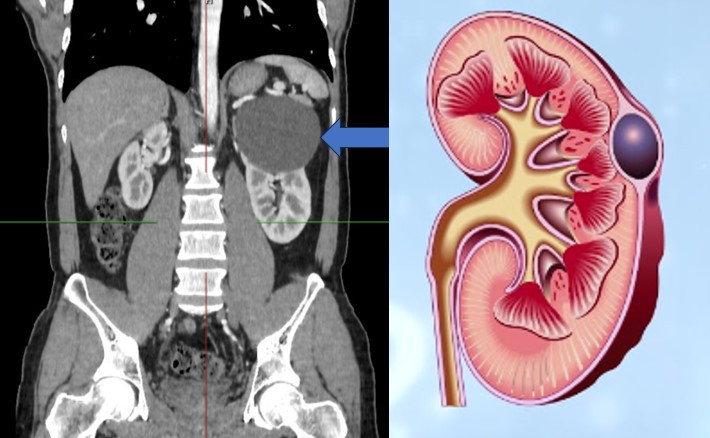

| Nang đơn thận là bệnh lý thường gặp trên lâm sàng. Đây là một bệnh lý lành tính phổ biến, đứng thứ hai trong nhóm bệnh thận có nang. Tỷ lệ mắc bệnh ở nam giới gấp đôi nữ giới và tăng dần theo tuổi. Bệnh thường khởi phát sau 40 tuổi. Ảnh minh họa: Internet |

Hình ảnh nang đơn thận

Bệnh có thể liên quan với tăng huyết áp do nang to chèn ép ảnh hưởng đến cơ chế điều hòa huyết áp tại thận. Hiếm gặp hơn là phát hiện nang thận thông qua sờ thấy khối ổ bụng khi nang quá to. Tất cả bệnh nhân có triệu chứng cần tầm soát kĩ bệnh lý ác tính tại nang.